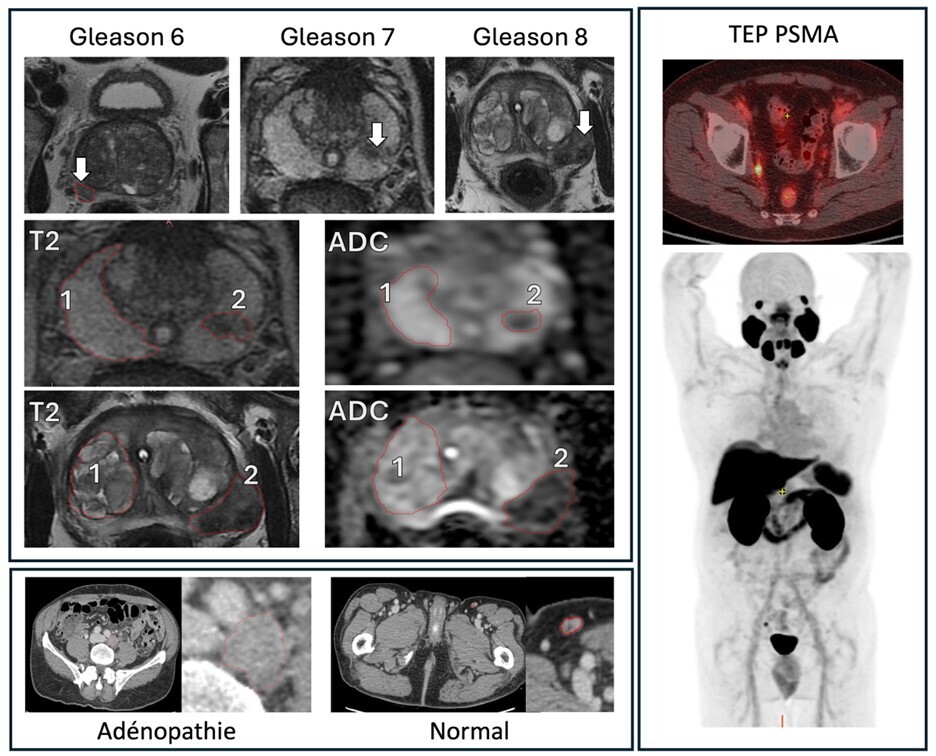

Lorsqu’ils sont détectés par imagerie, les nodules de moins de 6 mm ne sont pas suivis chez les patients à bas risque (non-fumeurs). Pour les nodules mesurant entre 6 et 8 mm, une TDM de contrôle est réalisée à six-douze mois. Enfin, une TEP-TDM au FDG (ou un scanner ou une biopsie) est indiquée pour les nodules pulmonaires solitaires solides de plus de 8 mm de diamètre (selon les guidelines de la Fleischner Society) avec de bonnes performances pour différencier les lésions bénignes et malignes.12 Un exemple de nodules pulmonaires solitaires solides visualisés sur la TDM thoracique et une TEP-TDM au FDG de suivi est présenté  en figure 3. La détection peut cependant être limitée par des faux positifs et négatifs dus à des facteurs techniques ainsi qu’aux éventuelles infections ou inflammations intercurrentes.

En cas de suspicion de cancer du poumon, il est essentiel d’obtenir une TDM diagnostique avec injection de produit de contraste iodé, qui permet de mieux délimiter une infiltration locale du cancer et améliore la visualisation du médiastin, des adénomégalies, de la paroi thoracique et des tissus mous. De plus, l’évaluation par TDM facilite la planification d’une biopsie pour la confirmation diagnostique par l’anatomopathologiste. Cependant, la TDM présente des limites dans l’évaluation des métastases ganglionnaires.13 Pour le bilan d’extension régional et à distance, la TEP-TDM au FDG est associée à l’IRM cérébrale. Cette approche permet de déterminer le stade de la maladie et d’identifier un site de biopsie optimal si une cible est plus accessible que la lésion pulmonaire.

Un patient de 65 ans, ancien fumeur avec un antécédent d’hypertension artérielle bien contrôlée, consulte pour une toux persistante. Une tomodensitométrie (TDM) révèle un nodule pulmonaire solitaire solide de 9 mm de diamètre. Il lui est ensuite recommandé de réaliser une tomodensitométrie par émission de positons (TEP-TDM) au fluorodésoxyglucose (FDG).

Pourquoi ?

Selon les recommandations de la Fleischner Society, pour un nodule pulmonaire solitaire solide de plus de 8 mm, il est recommandé de réaliser une TEP-TDM au fluorodésoxyglucose pour le caractériser, puis une biopsie ou un contrôle par TDM à trois mois, aussi bien chez les patients à faible qu’à haut risque.12